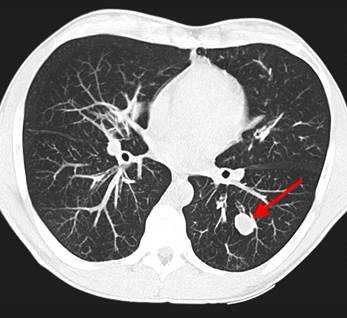

У пациента был выявлен раковый узел в 6 сегменте нижней доли слева. После резекции путем гистологического исследования верифицирован плоскоклеточный рак легкого. Томография в данном случае не дала типичную картину злокачественного новообразования.

Периферический рак легких на КТ выглядит как очаг либо узел, расположенный на периферии органа вдалеке от корня. Обычно он имеет однородную структуру, в некоторых случаях с участками некроза, обызвествлениями и кровоизлияниями в паренхиму. Края типичной раковой опухоли неровные, с множественными «спикулами» за счет лимфангиита. При расположении вблизи плевры образование деформирует ее и подтягивает к себе. Размеры его различны - от очага (3-10 мм) до узла (10-50 мм и больше).

Типичный периферический рак легкого (аденокарцинома) на МСКТ. Справа в 6 сегменте легкого выявлен плотный мягкотканный узел со спикулами, деформирующий и подтягивающий к себе междолевую плевру.